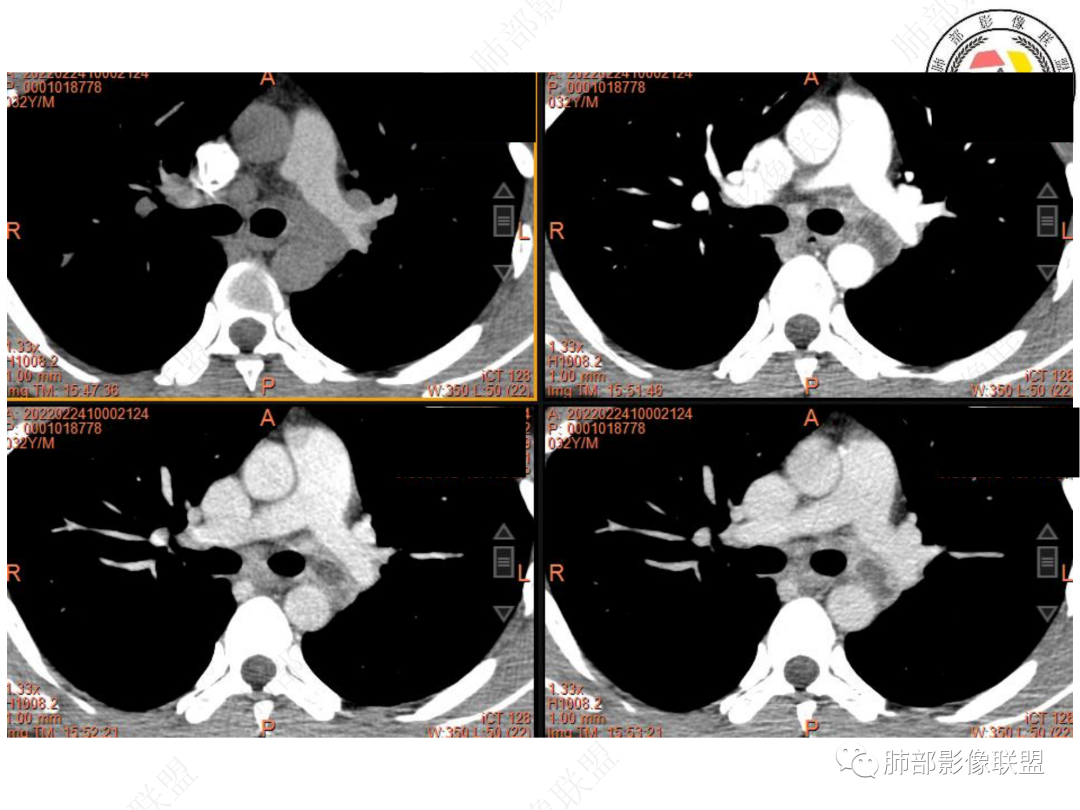

1. 青年男性,偶然发现左肺下叶结节影,左肺门及纵隔内多发淋巴结肿大,并坏死。

3. CT示左肺下叶背段孤立实性密度结节影,边缘比较清楚光滑,总体呈现膨隆感,未见分叶毛刺,少张力,部分层面病灶边缘呈现较清楚磨玻璃样密度影,并于磨玻璃影病灶内可见多发小空泡,未见钙化或空洞,增强后病灶显示不均匀强化,未见低密度液化区。未见卫星病灶。

左肺门及纵隔内多发淋巴结肿大,大部分淋巴结显示融合,强化不均匀,内见低密度区,疑液化坏死。纵隔内淋巴结部分周围脂肪间隙不清晰。大血管及左肺主支气管未见受侵改变。

5. 此病例青年男性,纵隔淋巴结环形强化,易先入为主诊断结核。但左肺下叶背段病灶密度均匀,强化明显,整体具备膨隆感,缺少炎性病灶的平直征,病灶周围未见卫星灶,应想到新生物可能。纵隔及左肺门肿大淋巴结,虽有部分淋巴结环形强化特点,但是部分淋巴结周围血管脂肪间隙小时、密度增高,强化明显。至此,亦可与结核的环形强化区分开来。尽管患者年轻,但恶性征象出现时,仍应当高度警惕。